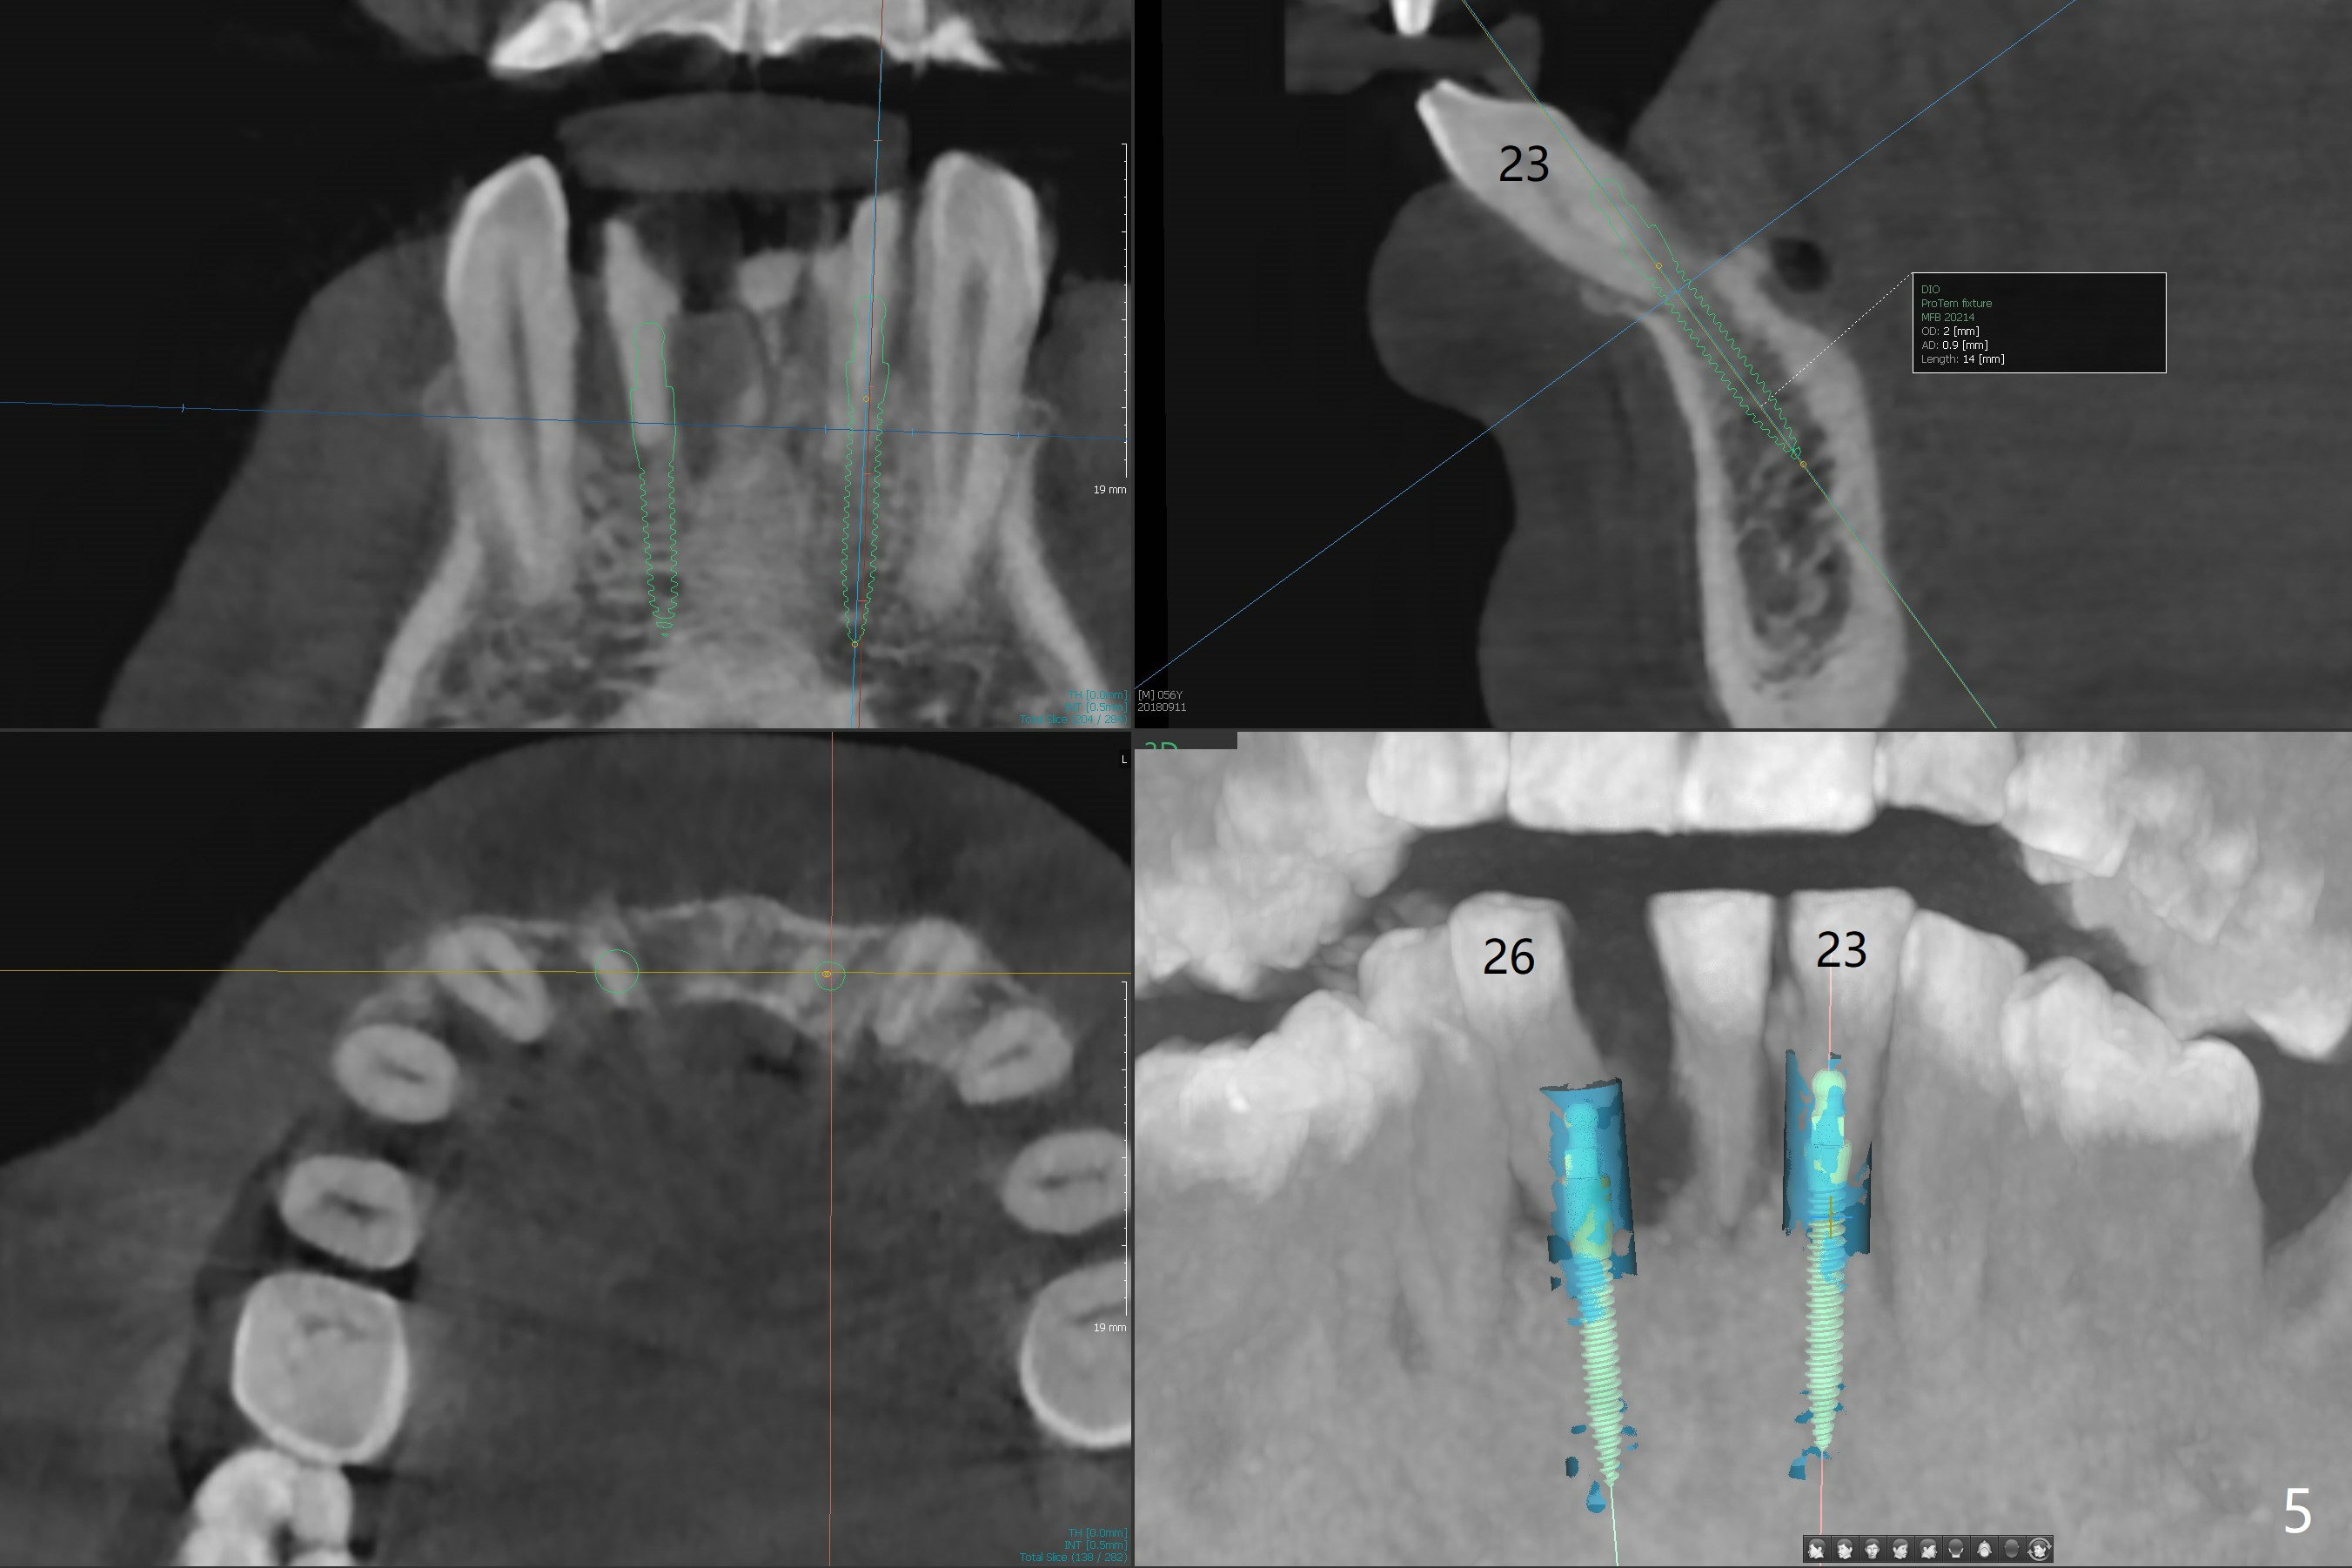

A 56-year-old man is a dental phobic. He finally seeks treatment because of loss of the tooth #25 with air leakage during speech (Fig.1). If the remaining lower incisors are stable after scaling and root planing, a 2.5 or 2.0 mm 1-piece implant will be placed in the narrow edentulous space (Fig.2). The implant driver (green sleeve) may touch the neighboring teeth, which need adjustment. If the worst incisor (#26 tender prior to SRP) is deemed to be non-salvageable, a 2.5 mm implant will be placed with a cantilever 2-unit FPD (Fig.3). If the tooth #23 is a survivor, two of 2.5 or 2.0 implants will be placed at #24 and 26 with a subsequent FPD (Fig.4). If the remaining incisors are all questionable in prognosis, two implants will be placed in the ends with a FPD (Fig.5). After SRP, the tooth #26 is less tender; the patient is ok with its extraction, but insists on saving #23 and 24. If 2 implants are to be placed at #25 and 26, they need to be 2 mm in diameter (Fig.6) with risks of injuring the neighboring teeth. It appears that it is more reasonable to have a single implant, slightly larger (2.5 or 3 mm), at #26, with the coronal end slightly mesial (Fig.7) with a cantilever bridge. If the teeth #23 and 24 fail in the future, a normal one will be easily converted.